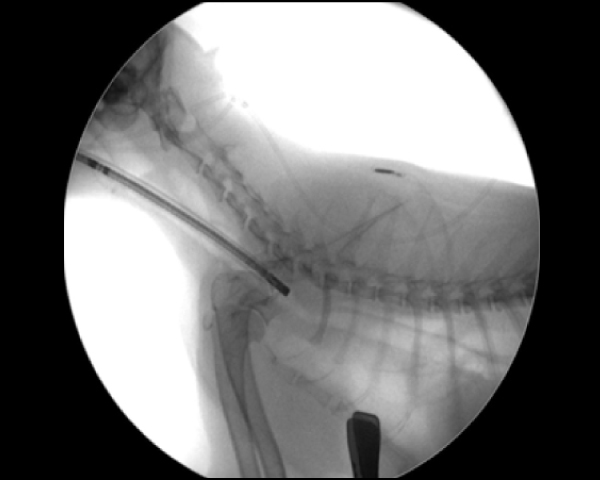

Cアームを用いたバルーン拡張術

内視鏡の位置をCアームで確認し正確に場所の把握が可能